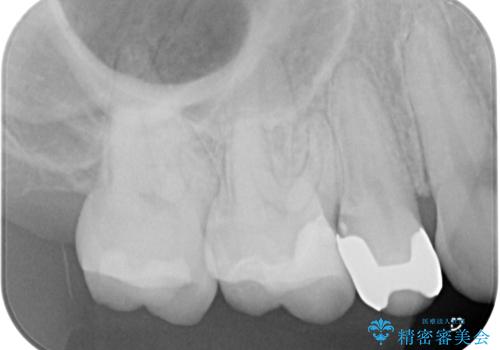

歯と歯茎の間に圧排糸と言われる糸を入れてシリコーン印象材にて精密な型どりをしました。

セラミックインレーの装着時には、唾液の侵入を防ぐために、ラバーダム防湿を行いました。

見た目、機能面共に大変喜んでいただきました。

歯と歯の間の虫歯をコンポジットレジンや保険のメタルインレーで治すと段差ができたりして清掃性が悪くなるので、セラミックインレー修復やゴールドインレー修復などの適合の良い詰め物で治療することをオススメします。